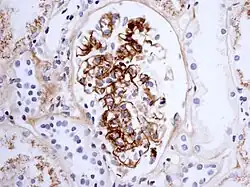

Morphology

Histologically, IgA nephropathy may show mesangial widening and focal and segmental inflammation. Diffuse mesangial proliferation or crescentic glomerulonephritis may also be present. Immunofluorescence shows mesangial deposition of IgA often with C3 and properdin and smaller amounts of other immunoglobulins (IgG or IgM). Early components of the classical complement pathway (C1q or C4) are usually not seen. Electron microscopy confirms electron-dense deposits in the mesangium that may extend to the subendothelial area of adjacent capillary walls in a small subset of cases, usually those with focal proliferation.

The disease derives its name from deposits of immunoglobulin A (IgA) in a granular pattern in the mesangium (by immunofluorescence), a region of the renal glomerulus. The mesangium by light microscopy may be hypercellular and show increased deposition of extracellular matrix proteins. In terms of the renal manifestation of Henoch–Schönlein purpura, it has been found that although it shares the same histological spectrum as IgA nephropathy, a greater frequency of severe lesions such as glomerular necrosis and crescents was observed. Correspondingly, HSP nephritis has a higher frequency of glomerular staining for fibrin compared with IgAN, but with an otherwise similar immunofluorescence profile.[4]